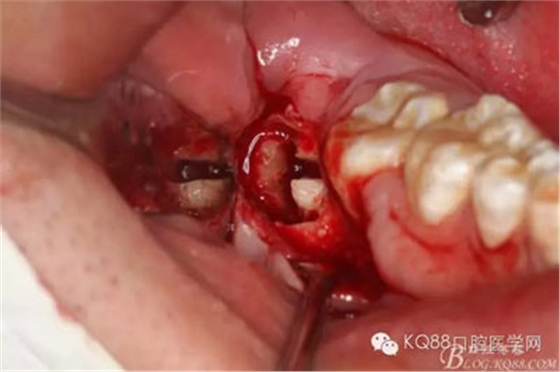

圖6.切開(kāi)、翻瓣

圖7.粘膜瓣似乎粘連,非常難翻,結(jié)果48還在骨頭里,頰側(cè)骨壁沒(méi)缺失呀,CBCT有問(wèn)題?

圖8.不管它,眼見(jiàn)為實(shí),去骨,發(fā)現(xiàn)48與周圍骨質(zhì)沒(méi)有界限,幾乎完全粘連